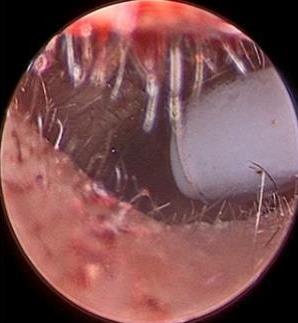

• 医用生物蛋白胶应用于耳内镜下鼓膜修补术的临床疗效

摘要:目的 分析医用生物蛋白胶应用于耳内镜下鼓膜修补术的临床疗效。方法 回顾性分析2022年10月-2023年10月该院收治的60例单纯鼓膜穿孔患者的临床资料,根据手术方法不同,将患者分为研究组和对照组,各30例。研究组术中使用医用生物蛋白胶粘合残余鼓膜和修补材料;对照组术中采用明胶海绵覆盖修补鼓膜。观察两组患者术后的鼓膜愈合情况(鼓膜愈合率、愈合时间、干耳时间和外耳道上下径)和并发症发生情况;于手术前后,采用纯音测听法(500、1 000、2 000、4 000 Hz),测量两组患者气导阈值,观察听力改善程度;采用视觉模拟评分法(VAS)评分,评估患者术后疼痛程度。结果 两组患者术后鼓膜愈合率、愈合时间、外耳道上下径和并发症发生率比较,差异均无统计学意义(P > 0.05)。研究组术后平均气导听阈明显低于对照组,差异有统计学意义(P < 0.05)。研究组术后干耳时间短于对照组,术后第1天疼痛VAS评分明显低于对照组,差异均有统计学意义(P < 0.05)。结论 医用生物蛋白胶应用于耳内镜下鼓膜修补术,可有效地降低气导听阈,缩短干耳时间,减轻患者疼痛,且不增加并发症发生率,值得临床推广应用。